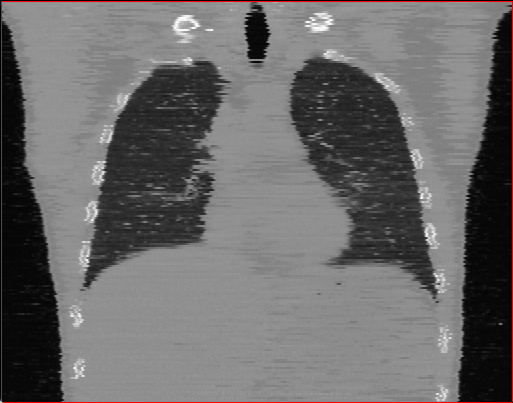

Chest Region

1×1×11\times 1\times 1

mm

384×384×384384\times 384\times 384

Figure 3: MAISI-v2 segmentation-guided results for small to large volume size and three different regions.